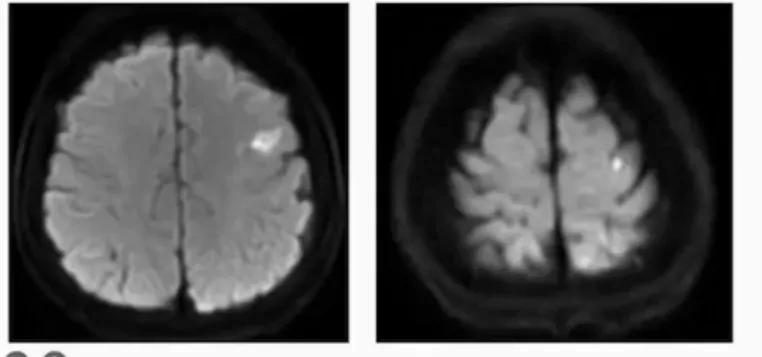

★ 左侧 ICA 狭窄